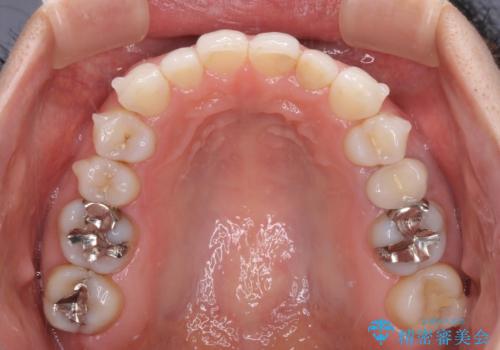

軽度の叢生をインビザライン・ライトで解消

- 前歯が気になるとのことで来院された患者様です。

歯列不正は軽微であったため、インビザライン・ライトにより、費用を抑えて矯正治療を行うこととしました。

短期間で気になる前歯の歯列を改善することができました。